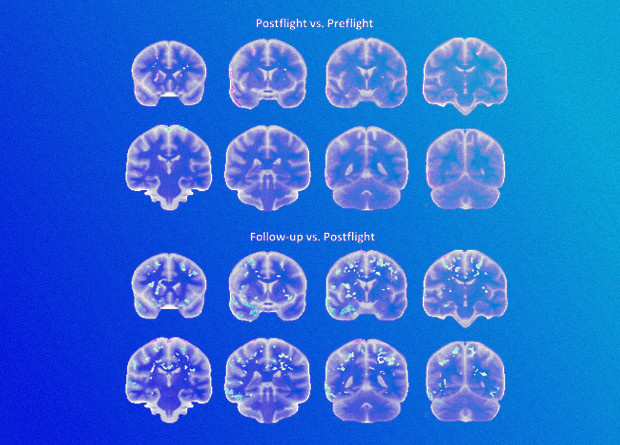

У людей, которые несколько месяцев провели в условиях пониженной гравитации, меняются объем и структура различных участков мозга. В исследованиях астронавтов и космонавтов с МКС уже было показано, что мозг при состоянии, близком к невесомости, смещается в черепе вверх, объем серого вещества в коре лобных и височных долей снижается, как и объем белого вещества. Также происходит перераспределение спинномозговой жидкости: ее становится больше в желудочках мозга, а в подпаутинном пространстве она скапливается у основания мозга и выше присутствует в сравнительно небольших количествах. Принято считать, что это служит одной из причин структурных изменений нервной ткани при микрогравитации.

Также есть предположение, что объем белого и серого вещества снижается из-за нейродегенерации — отмирания части нервных клеток. В таком случае изменения в строении мозга космонавтов, скорее всего, будут перманентными или по крайней мере долгосрочными: если образование новых нейронов у взрослых людей и идет, то полностью покрыть потери клеток в данном случае оно вряд ли сможет. Однако исследований, в которых за изменением структуры мозга побывавших в космосе следили хотя бы несколько месяцев после возвращения на Землю, практически нет. Немногочисленные работы по этой теме показывают, что гипофиз космонавтов меняется надолго, но о других частях головного мозга информации меньше.